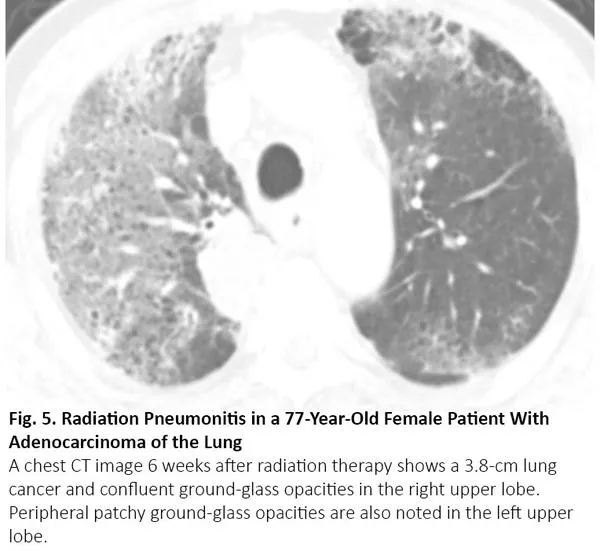

肺癌患者在病程中可能出现与COVID-19类似的CT异常,但这些异常是由于其他原因,如病毒性肺炎、癌症复发和间质性肺病。病毒性肺炎,特别是流感肺炎,在胸部CT上可表现为双侧磨玻璃样影和实性病变,胸部CT上位置分布相似10(图3),秋冬流感高发时,利用放射学检查结果来鉴别二者可能有问题。COVID-19 CT比流感肺炎CT更多见小叶间隔增厚及圆形阴影(典型肺周分布),但肺结节和树芽征相对更少。11

图3. 流感肺炎